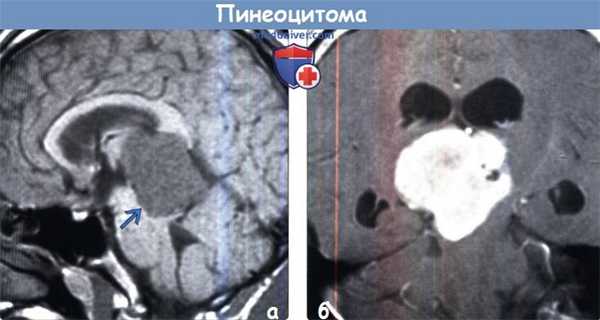

(а) МРТ, постконтрастное Т1-ВИ, аксиальный срез: в пинеальной области определяется объемное образование дольчатой, частично кистозной структуры, частично накапливающее контраст. Среди опухолей паренхимы эпифиза пинеоцитома встречается наиболее часто. При кистозном строении эти опухоли могут имитировать доброкачественную пинеальную кисту.

(б) МРТ, постконтрастное Т1-ВИ, ко-рональный срез: у пациента с пинеоцитомой определяется как периферический, так и более солидный характер контрастирования кистозного пинеального объемного образования. Также присутствует мелкий центральный очаг контрастирования по типу мишени.2. Стадирование и классификация пинеоцитомы:

(а) МРТ, Т1-ВИ, сагиттальный срез: определяется вариант структуры пинеоцитомы. Присутствует крупная дольчатая опухоль, четко отграниченная от окружающих тканей, которая вызывает обструктивную гидроцефалию вследствие компрессии сильвиева водопровода. Опухоль слегка гиперинтенсивна по отношению к СМЖ и умеренно гипоинтенсивна по отношению к ткани мозга.

(б) МРТ, постконтрастное Т1-ВИ, корональный срез: определяется выраженное контрастирование опухоли с умеренно гетерогенным его характером. «Вариантные» случаи предполагаемой пинеоцитомы необходимо дифференцировать с ОПЭПД, более агрессивной опухолью.д) Клиническая картина: